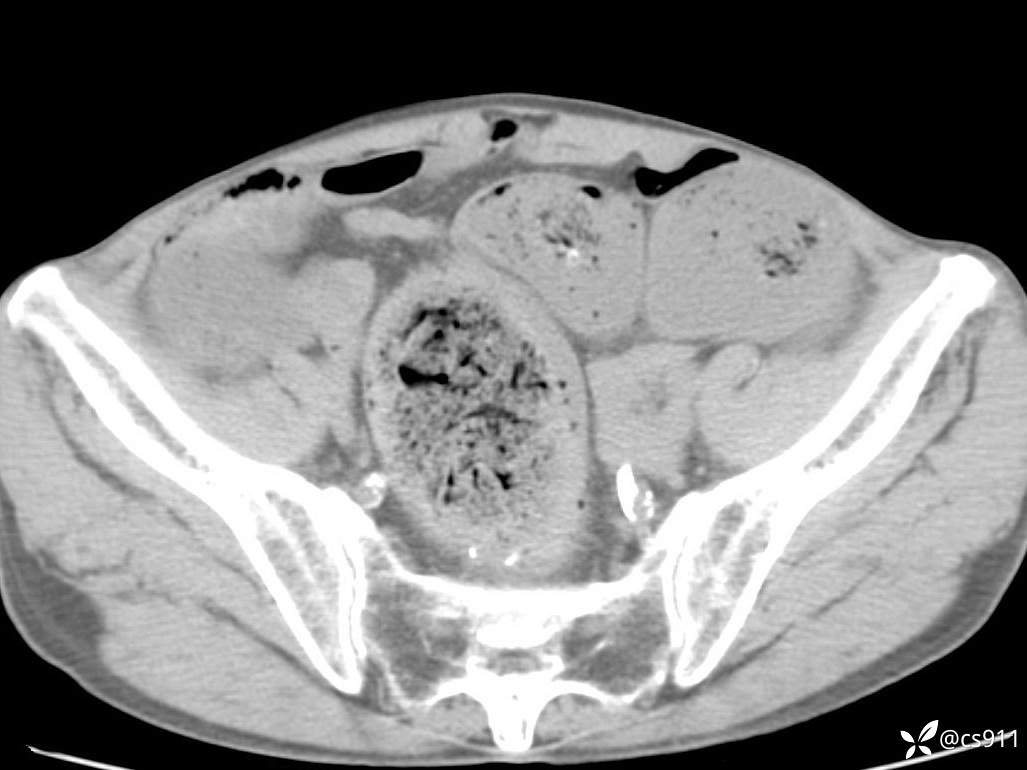

急腹症之急诊CT,原因?答案公布

男,77岁,腹痛、腹胀伴恶心呕吐1天。呕吐胃内容物,非喷射性呕吐,有咖啡色样胃内容物,诉有胃穿孔病史。查体:全腹平,下腹部压痛,全腹无反跳痛,叩诊呈浊音,移动性浊音阴性,肠鸣音减弱,1-2次/分。肛检:直肠未扪及明显肿物,可触及大量粪块。